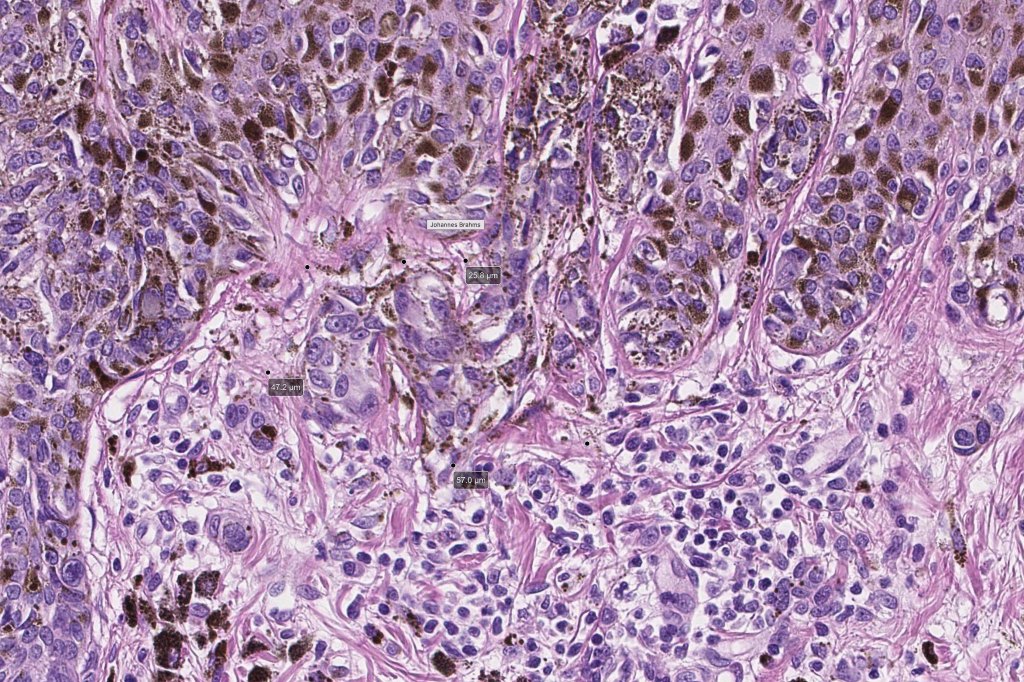

•Host response- eosinophilic & lamellar fibroplasia, increased vascularity, lymphocytic infiltration & pigment incontinence

Dysplastic nevus with early melanoma